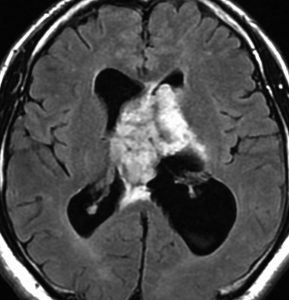

片側性水頭症

左尾状核から発生したものです。モンロー孔を閉塞して,片側性水頭症となっています。腫瘍がトリュフみたいにゴツゴツしているのも特徴です。

下のガドリニウム増強T1では,部分的に増強されます。

もちろん無症状ですが,年齢が若かったので全摘出しました。